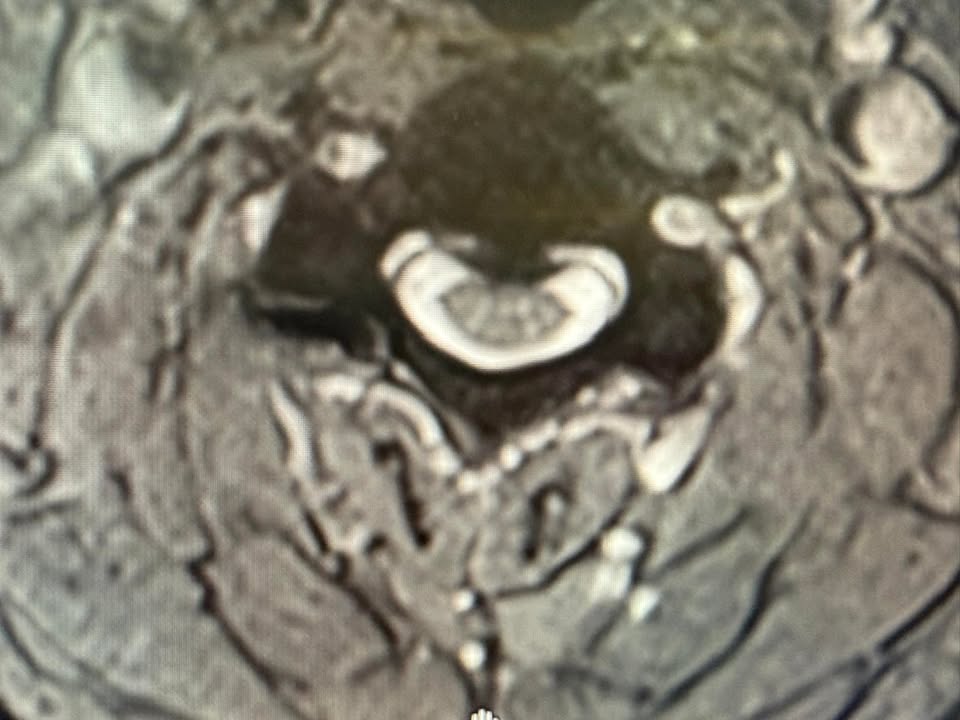

後來,他輾轉到台中中國醫藥學院,接受完整的神經學檢查,最後安排了頸椎核磁共振。這次,答案終於浮出水面——頸椎後縱韌帶鈣化症(OPLL),病變範圍從 C2 到 C4,壓迫了他的神經,甚至影響了交感神經。